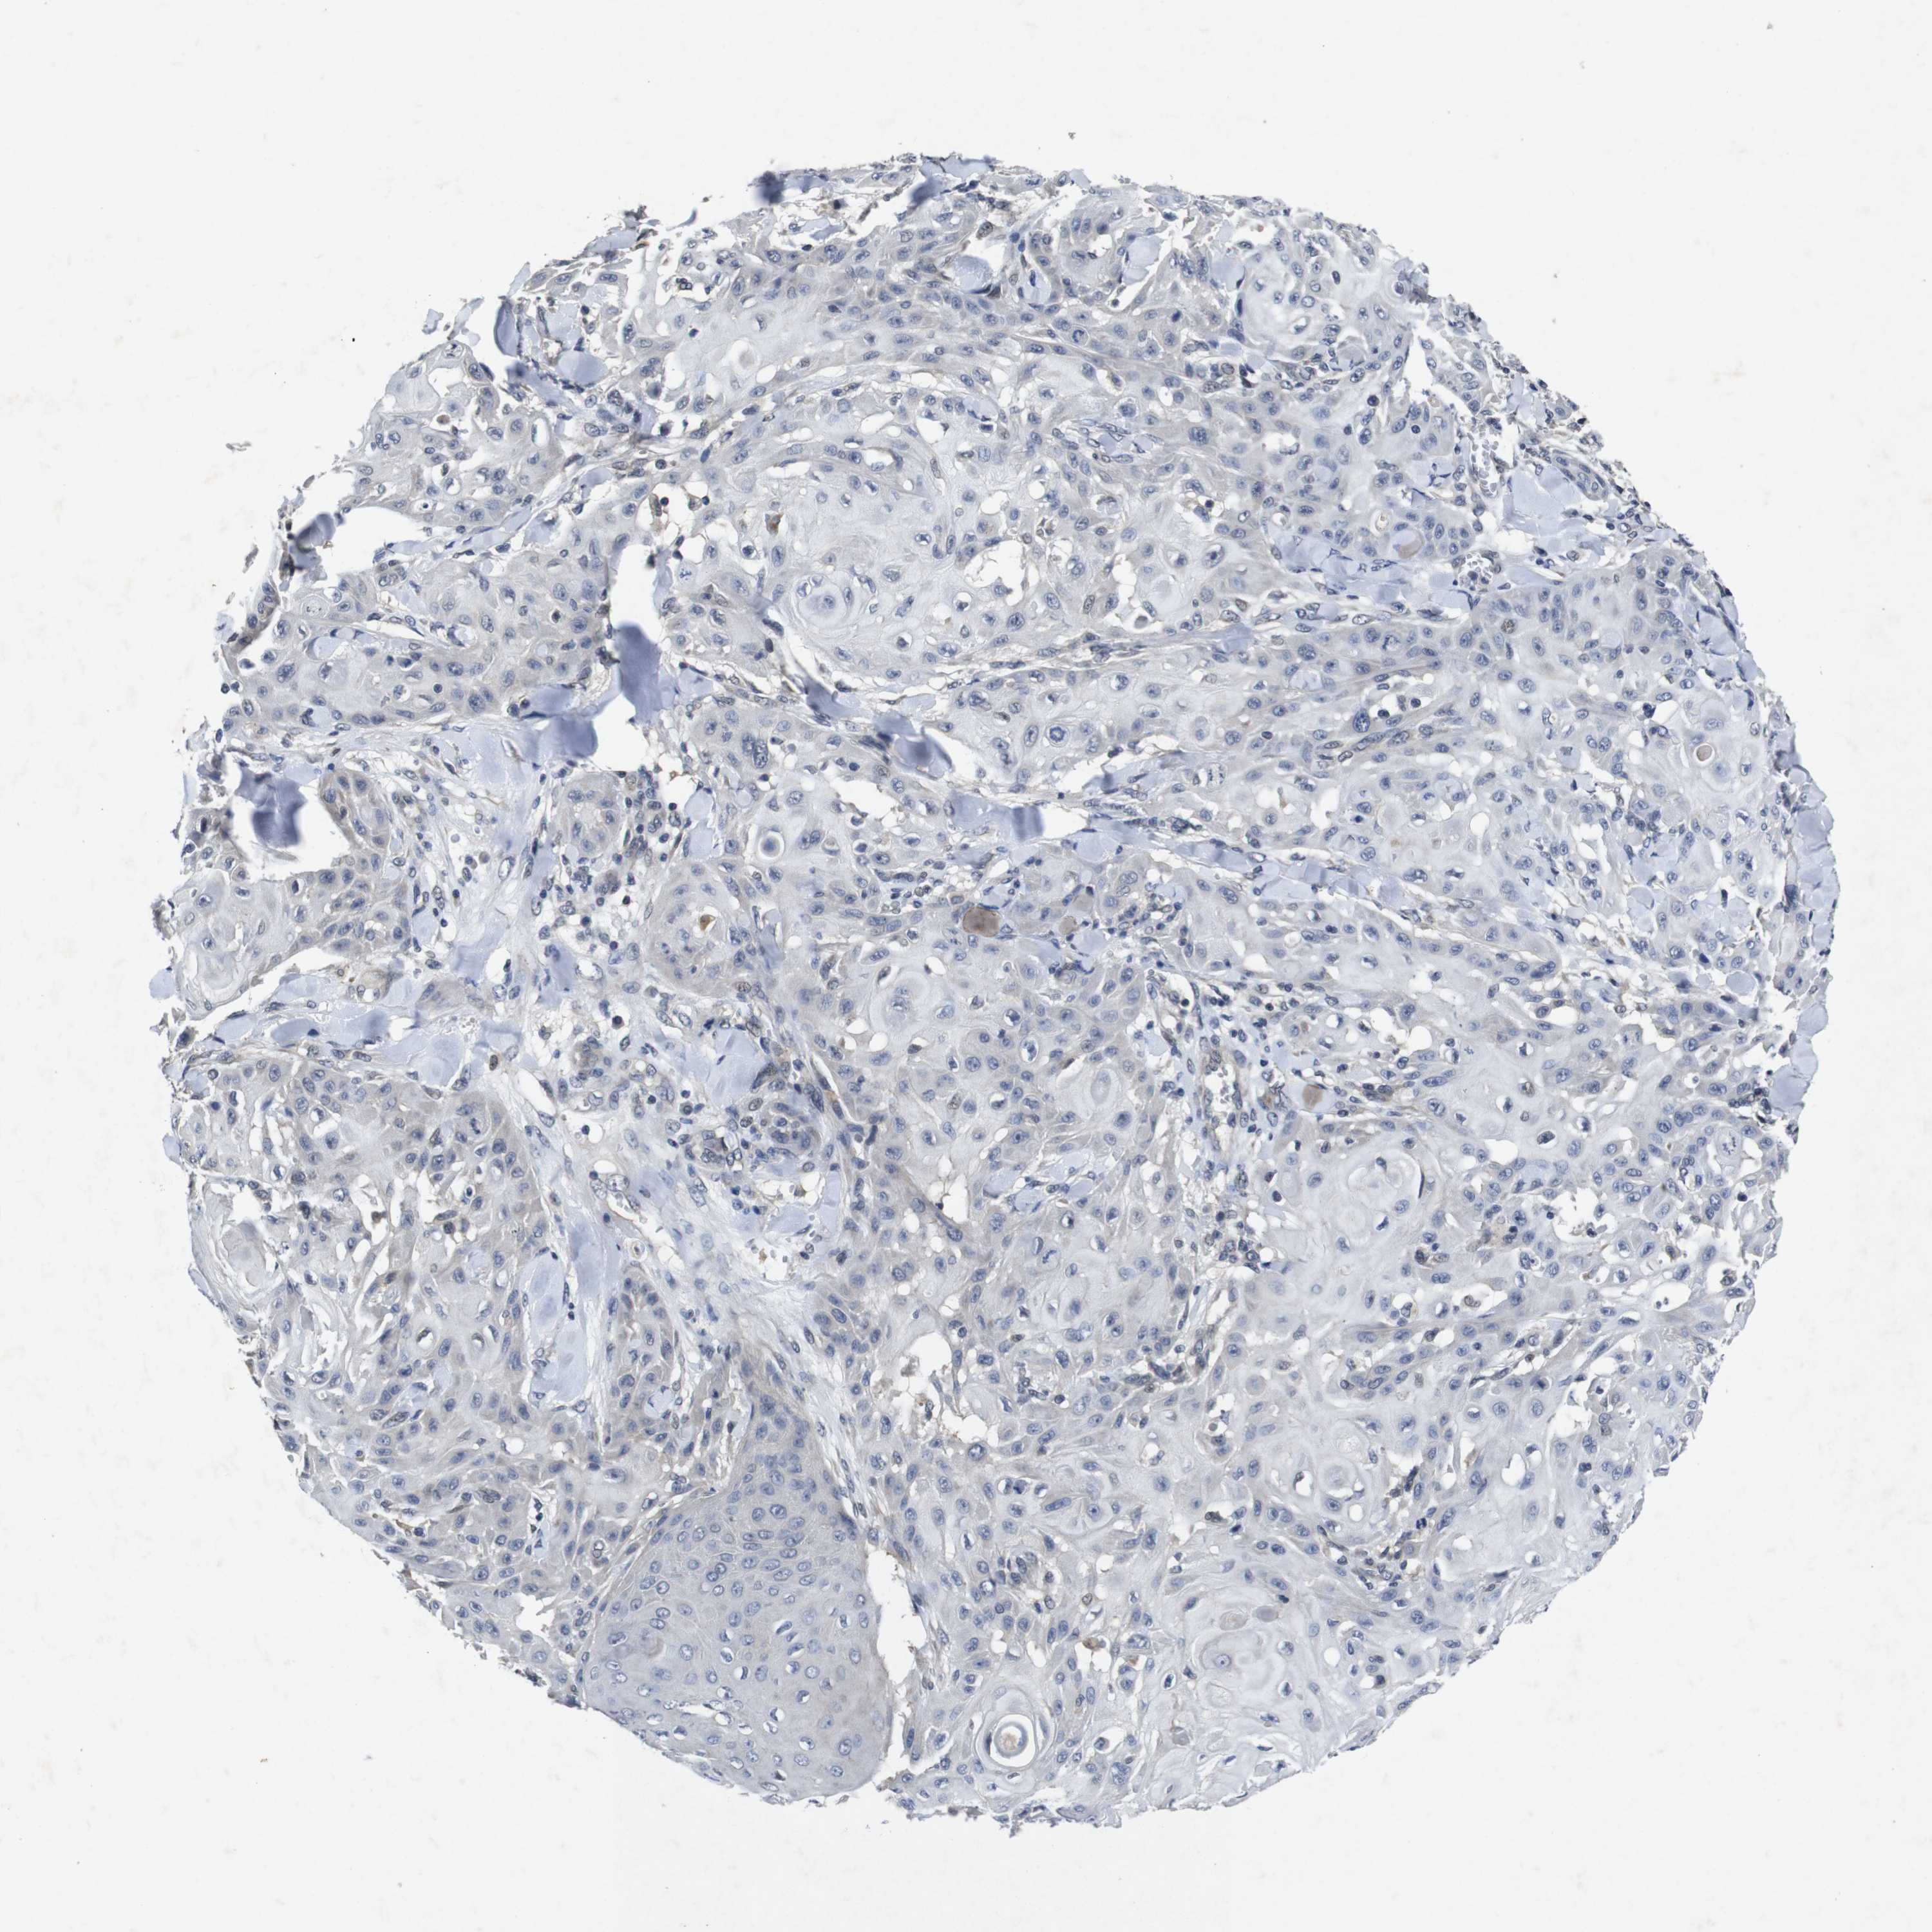

SKIN CANCER - Protein expressioni

A mouse-over function shows sample information and annotation data. Click on an image to view it in a full screen mode. Samples can be filtered based on level of antibody staining by selecting one or several of the following categories: high, medium, low and not detected. The assay and annotation is described here.

Antibody stainingi

Antibody staining in the annotated cell types in the current human tissue is reported as not detected, low, medium, or high, based on conventional immunohistochemistry profiling in selected tissues. This score is based on the combination of the staining intensity and fraction of stained cells.

Each image is clickable and will lead to virtual microscopy that enables deeper exploration of all samples and also displays staining intensity scores, fraction scores and subcellular localization as well as patient and tissue information for each sample.

Antibody HPA026441

Antibody CAB013090

Staining

High

Medium

Low

Not detected

Intensity

Strong

Moderate

Weak

Negative

Quantity

>75%

75%-25%

<25%

None

Location

Nuclear

Cytoplasmic/membranous

Cytoplasmic/membranous,nuclear

Squamous cell carcinoma, NOS